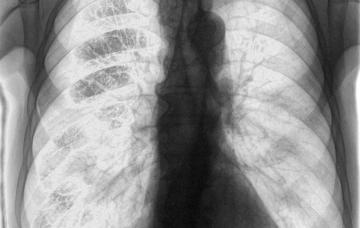

Diagnóstico de la tuberculosis

Para el diagnóstico de tuberculosis, además de los síntomas del paciente, se realizan pruebas sencillas como análisis del esputo y radiografía de tórax.